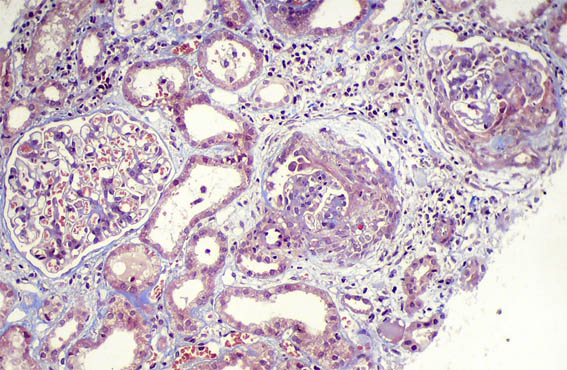

Figure 7. Masson's trichrome stain, X200.